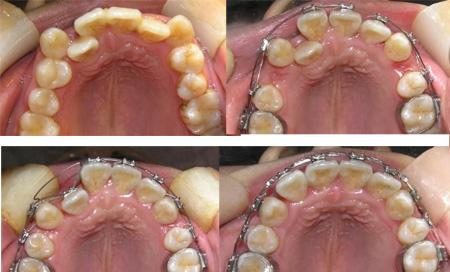

牙弓可以扩展吗 扩大牙弓是矫治牙列拥挤的主要方法之一。通过矫治器将牙弓的宽度或长度扩大,在牙弓上获得一定间隙,从而使拥挤错位的牙齿排列整齐。扩大上牙弓前段长度。可解除前牙反颌,... 牙齿矫正 公冶乐天 701 2023-11-25